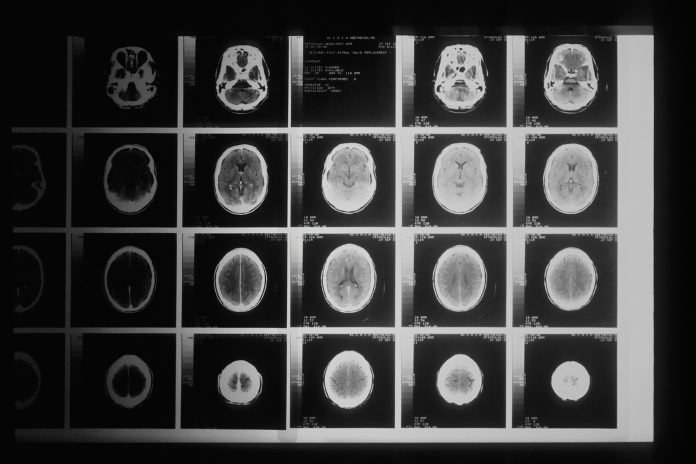

This study accesses and manipulates data from the Stanford CheXpert dataset3. This data came from over 225,000 different chest radiographs. The x-rays were collected from Stanford Health Care between October 2002 and July 2017 in inpatient and outpatient centers. This dataset includes over 200,000 images of frontal and lateral thoracic radiographs. The sheer size of the dataset contributes to the diversity and reach of this study. The dataset contains patients with a multitude of conditions, meaning this dataset would be applicable to many different respiratory or thoracic conditions and diseases. The dataset even accounts for patients with pacemakers or other support devices, making it even more implementable in a clinical setting. Additionally, the radiograph images were taken from a diverse set of patients further ensuring universality and accuracy.

This study includes convolutional neural network based diagnosis methods for the 14 different thoracic conditions included in the CheXpert dataset: enlarged cardiomediastinum, cardiomegaly, lung opacity, lung lesion, edema, consolidation, pneumonia, atelectasis, pneumothorax, pleural effusion, plural other, fracture, and support devices. Along with the condition stated in the data (or no finding, meaning no condition was present), the data’s columns included the path to the associated radiograph image, the sex of the patient, age, the view of the scan (frontal/lateral), and finally the type of radiation wave used for the x-ray (AP/PA). All of the above demographics, along with the type of condition, are crucial pieces of information and depending on each patient’s demographics, there are different approaches in examinations and diagnosis. Below are descriptions of each condition.